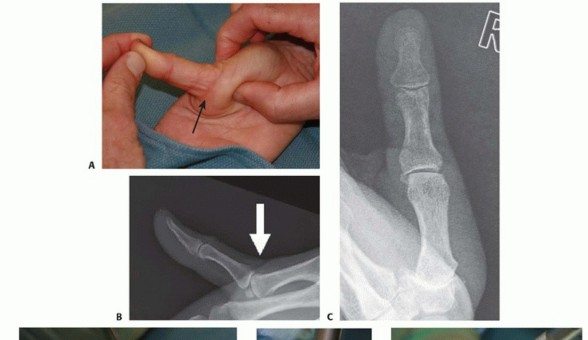

In traumatic cases, it is important to inquire about the mechanism of injury.If patients recall which way the thumb was “pointing” at the time of injury, it helps the examiner determine which structures were likely injured.With the ubiquitous presence of cell phone cameras and digital cameras, photos of the deformity right after the injury are often available and can be helpful in confirming the suspected injury.Was the joint dislocated and did it reduce spontaneously or with assistance from a coach, trainer, or the patient?How difficult was the reduction?Physical examination should include an assessment of ROM and grip and pinch strength, particularly in comparison with the contralateral thumb. Focal areas of tenderness should be ascertained. Residual tenderness along the volar plate may persist long after the injury.The examiner should observe the resting joint posture; dislocated joints exhibit obvious deformity.The examiner should check for open wounds and assess the vascular status. Open wounds or vascular compromise mandate emergent treatment.Limited or absent interphalangeal joint ROM suggests flexor pollicis longus tendon entrapment. Dislocated or painful MP joints will have limited ROM.Volar plate stability is assessed because instability must be recognized and treated appropriately to maximize outcomes.Severe collateral ligament injury is uncommon in conjunction with volar plate instability but must be recognized and treated where indicated.An acute dislocation is rarely subtle, but when patients present with chronic instability symptoms, there may be guarding against full joint extension and soft tissue thickening in areas of chronic pathology.

FIG 2 • X-rays showing MP joint dislocation on AP (A) and lateral (B) films. (continued)